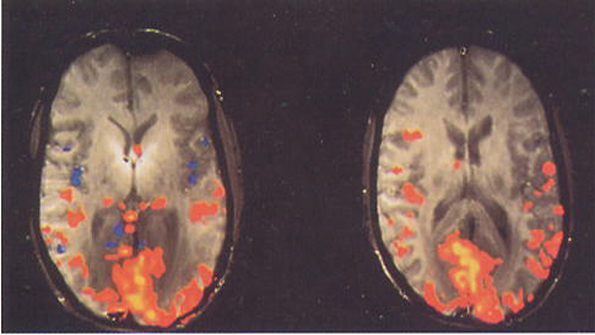

The synthesized RF pulses provide a coherent image (see the figure) compared to the first, conventionally obtained image. The scans were performed in conjunction with a GE Signa EXCITE 3 T MR Scanner. The accuracy of the DAC board provided a reference signal that compensated for the phase of off-resonance frequencies used to excite different slices.